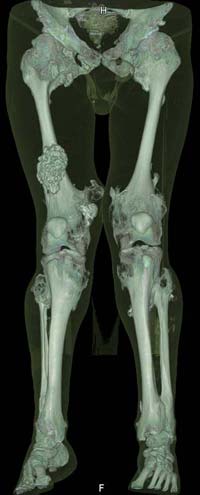

Oбратился больной 30 лет с хондродисплазией, множественными деформациями и экзостозами. Сгибательно-приводящие контрактуры Т/Б сустав, поясничный лордоз.

Интелектуально развит, работает програмистом. Болей нет. Анализы крови в пределах нормы, понижен кальций (общий Ca 1.62, N от 2.3 до 2.75;ионизорованный 0.67, N от 0.7 до 1.07) и щелочная фосфотаза -7.9. По данным КТ, оптическая плотность диафизов 150 - 200 NU (N в его возрасте 300 -350NU) метафизарный остеопороз от 100NU до отрицательных величин - 80 NU.

Больной настоятельно просит об исправлении деформаций и удаления экзостозов области коленных суставов.

30 years old male with chondrodysplasia and multiple exostoses admitted.Multilevel deformities, flexion-adduction limitation of hip ROM, lumbar lordosis. Intellectually developed, working in some software company. Painless. Blood tests are normal, except low Calcium (total serum Ca 1. 62, N is 2.3 - 2.75; ionized 0.67 N is 0.7 -1.07) and low alkaline phosphatase 7.9. Diaphysis bone density is about 150 - 200 NU (N in his age is 300 - 350NU). Metaphis osteoporosis is from 100NU to minus 80 NU.

The x-ray is satisfactory for analysis. In The AP view, The knee and ankle should be exactly anterior and the patella should be facing forward, then we can measure the deformity in the AP. Another lateral view of the whole lower limb should be taken, so we can correct 6 dimensions (X, Y and Z axes and Alpha, Beta and Gamma rotation).

But it seemes to me that he has distal femoral valgus and may be also distal tibial. But anyway, we have to measure a good x-ray (lateral distal femoral angle, Medial proximal tibial angle and also the distal tibial angles).

After Dr Elbatrawy saw the CT scans he added - the case has multible exostosis and the ulna also may need lengthening on both sides; he will need follow up, as one of the multible exostosis may transform to Chondrosarcoma on top of its cartilagenous cap. It is a common problem associated with this condition.